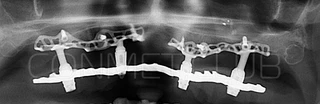

2. После этого произвели компьютерное моделирование самого имплантата и фиксирующих элементов. Примечательно, что в абатментах, использовался отлично зарекомендовавший себя и проверенный десятилетиями интерфейс КОНМЕТ! В результате получили несколько специальных файлов, позволяющих не только сделать сам имлантат, но еще до операции изготовить и сами зубы. Данные файлы передали в изготовление на специальном 3D оборудовании.

Имплантат напечатали из особого, биосовместимого, медицинского титана на предприятии имеющим соответствующую медицинскую лицензию. Толщина имплантата составила 0,8 мм, а вес всего несколько грамм!

Сама же операция длиться 20-50 минут в зависимости от количества утраченных зубов. В процессе этой операции, после проведенной местной анестезии, делается разрез на слизистой, она приподнимается и субпериостальный имплантат укладывается на кость. После этого рана фиксируется несколькими швами и все! Через 10-14 дней мягкие ткани срастаются и надкостница надежно удерживает имплантат на месте. Нет необходимости ждать несколько месяцев, как это бывает в случае с внутрикостными винтовыми имплантатами.

Новые, искусственные зубы фиксируются к этому имплантату стандартными, трансокклюзионными винтами на 1-14 день (в данном клиническом случае на 5 сутки) и по существу являются несъемными!

Посмотрите на небольшом клиническом примере новый подход к конструированию имплантата по сравнению с имплантатами описанными в начале этой статьи.